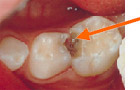

むし歯はどうしてできるの?

むし歯菌は糖分を栄養にして、水に溶けにくい歯垢(プラーク)=細菌のかたまりをつくり、この中の細菌が糖分を分解して酸をつくります。

酸によって歯の表面は溶け始め、この状態が続くと歯には穴があいてきます。これがむし歯です。